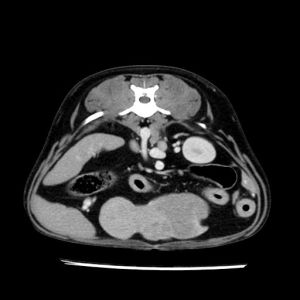

La lesione focale epatica , la ceus,la Tac e il chirurgo .